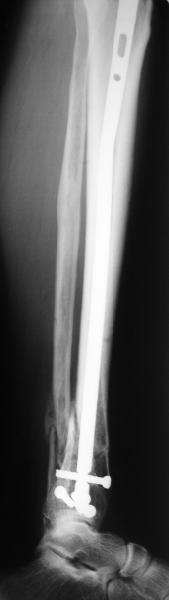

Направили к нам пациентку 35 лет с переломом дистального отдела костей голени.

У нас сделали снимок сзахватом обоих суставов - еще и проксимальный метафиз сломан. Чем бы у вас фиксировали такой перелом? Как его правильно закодировать по классификации АО?

Можно либо как два перелома - 41A+42B. А можно как один сегментарный 42С.

Today you have a complex fracture for classification.

Probably you need take a combination of two diferents fractures in the same bone.

41.A2.1 for a proximal fracture

42.B1.3 for a distal fracture

Is very difficult take an exactly AO/OTA group for a good classification Probably the locked IM nail is a good option.